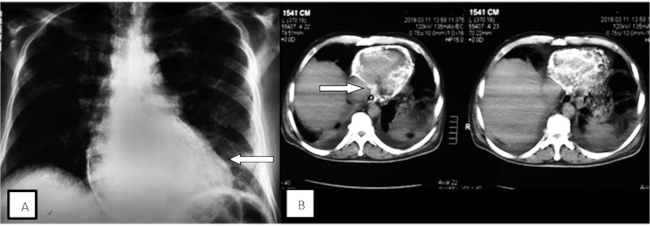

En la radiografía de tórax, se observó grave calcificación pericárdica circunferencial (Figura 1A). El ecocardiograma Doppler, además de evidenciar la calcificación del pericardio, detectó fisiología constrictiva. La tomografía de tórax confirmó la calcificación del pericardio en toda su circunferencia, con un patrón “de cascara de huevo” (Figura 1B), y la presencia de ganglios mediastinales, parahiliares, axilares y mesentéricos calcificados, en rango no adenomegálico.